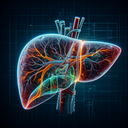

МРТ печінки

МРТ печінки – це неінвазивний метод обстеження, який використовує магнітне поле та радіохвилі для отримання детальних зображень печінки і навколишніх структур. Це допомагає виявити різні захворювання та стани, пов’язані з печінкою. ### Показання для проведення МРТ печінки: - Виявлення і оцінка пухлин (злоякісних або доброякісних)...